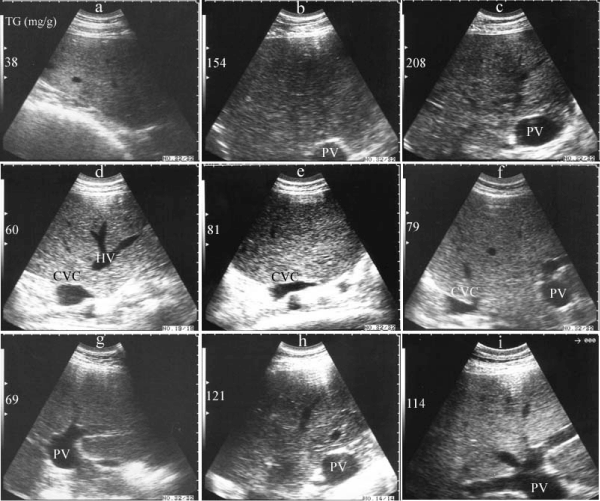

| Figure 1: Hepatic ultrasonograms in 3 cows during the transition period. Images were taken 3wk before expected parturition (a, d, g), at parturition (b, e, h) and 3wk after parturition (c, f, i). With increased liver triglyceride (TG) content in cow 1 (a, b, c), hepatic ultrasonography showed a gradual increased echogenicity with vascular blurring. In cow 2 (d, e, f), with increased hepatic TG content hepatic echogenicity increased at parturition and then declined 3wk after parturition parallel to TG content. In cow 3 (g, h, i), hepatic echogenicity increased also with increased hepatic TG content. |